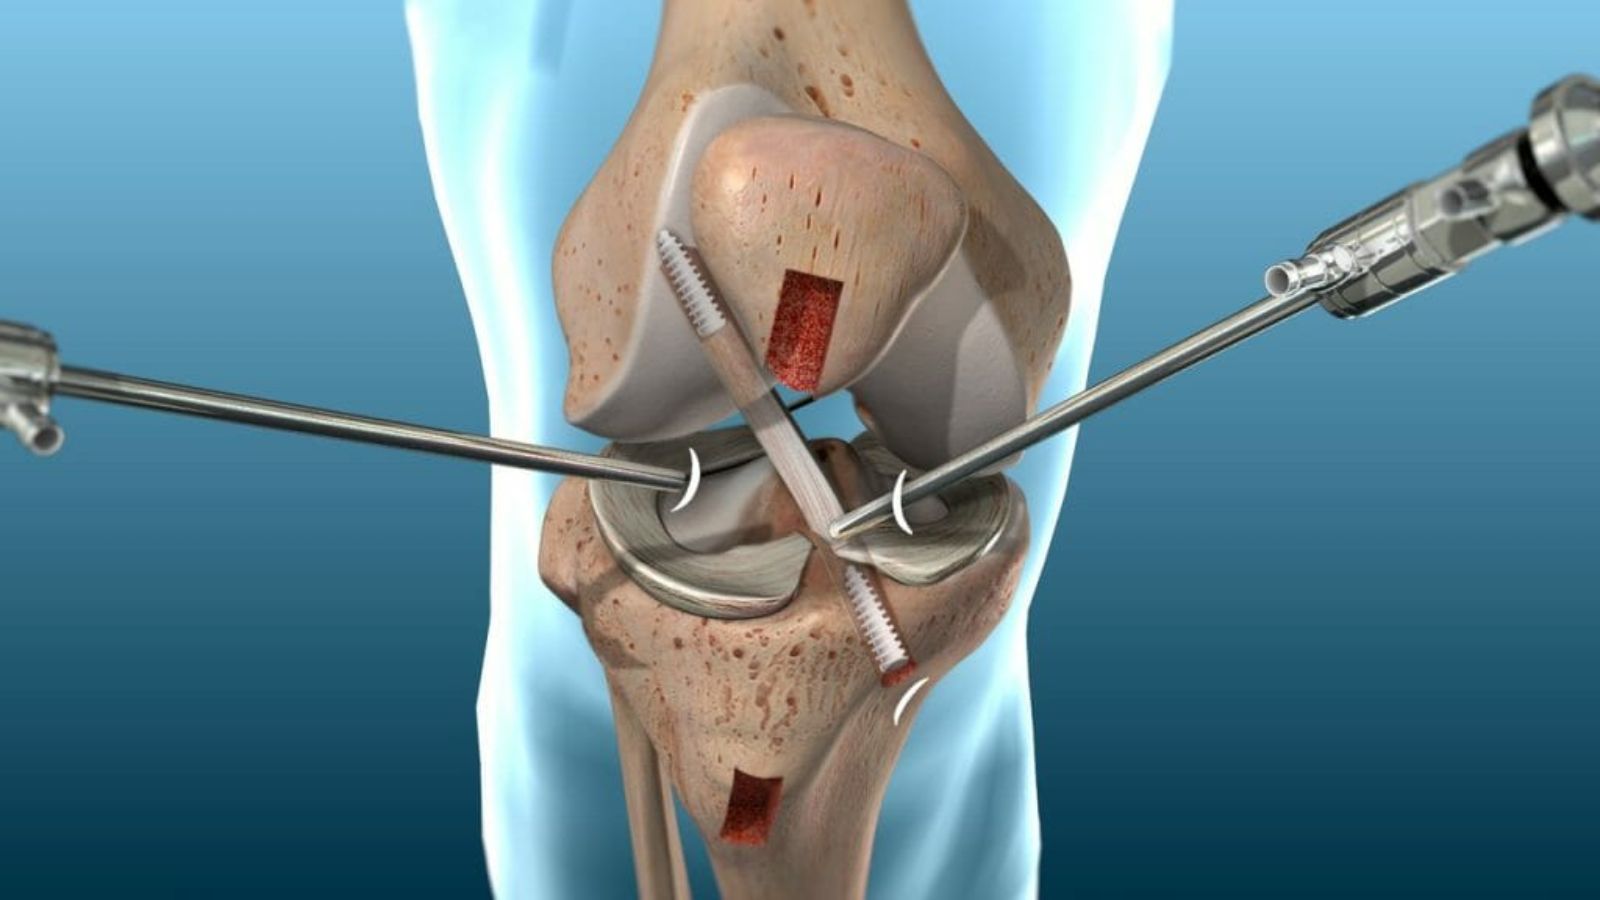

Quando a lesão no menisco é extensa ou não responde ao tratamento conservador, o ortopedista pode indicar a cirurgia como melhor alternativa. O procedimento mais comum é a artroscopia do joelho, uma técnica minimamente invasiva que utiliza pequenas incisões e câmeras para visualizar a articulação por dentro e reparar ou remover a parte lesionada.

Essa abordagem cirúrgica é recomendada principalmente em pacientes jovens, ativos ou atletas que precisam recuperar rapidamente a estabilidade do joelho. Além disso, em casos de bloqueio articular ou dor persistente que limita as atividades diárias, a intervenção cirúrgica pode proporcionar alívio significativo e melhor função do joelho.